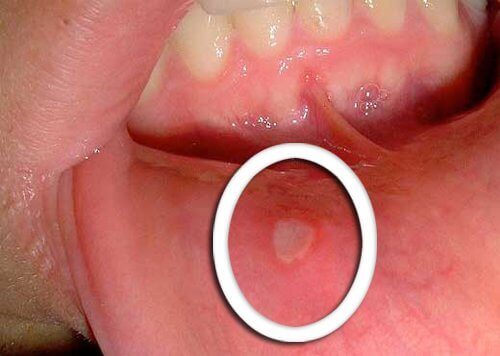

Suussa näkyvät fyysiset muutokset

- Aikaisin oire nielusyövästä ovat pienet haavaumat, jotka eivät parane.

- On tyypillistä, että kielessä alkaa näkyä punaista tai valkoista, tai sitten tätä ilmenee ikenissä ja huulissa.

- Kiinnitä huomiota kaikkiin epätavallisiin muutoksiin, jotka eivät katoa muutamassa päivässä, ja kerro niistä lääkärille.